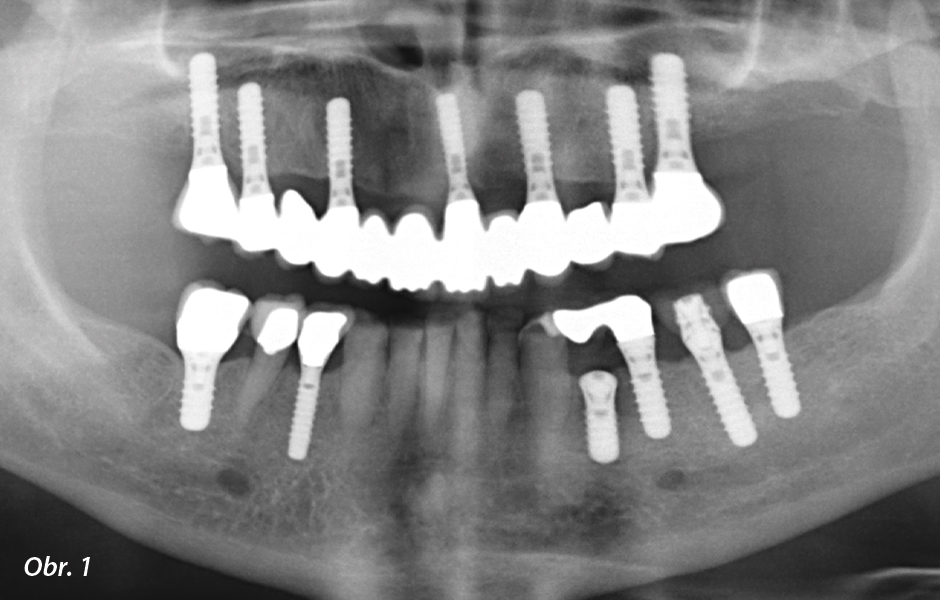

68letá pacientka se dostavila ke konzultaci za účelem prvotního vyšetření s přáním estetického ošetření dolních frontálních zubů fazetami. Pacientka byla v minulosti v horní čelisti ošetřena šroubovanými můstky na sedmi implantátech a v laterálních úsecích dolní čelisti v oblasti zubů 34–37, 44 a 46 rovněž rekonstrukcemi nesenými implantáty. Vlastní zuby ještě přetrvávaly pouze v dolní frontální oblasti (33–43) a v oblasti dolního pravého premoláru (obr. 1). Pacientka vykazovala zřetelné známky atrice a abraze na dolních frontálních zubech (obr. 2) a deficit ve vertikální vzdálenosti okluze (obr. 3). V dolním frontálním segmentu byla přítomna kompenzační repozice alveolárního hřebene ve směru okluzní roviny, na což jasně poukazoval rozšířený pruh keratinizované gingivy (obr. 4) (Bartlett & Smith 2000; Berry & Poole 1976; Ceric-Nagas & Ergun 2015; Manfredini & Poggio 2016). Toto je velmi nepříznivé pro naplánování rekonstrukcí, protože v důsledku toho je ve většině případů přítomno příliš málo místa v okluzi (Mericske-Stern 2007). Veškeré dolní frontální zuby byly ve statické okluzi po kontrole fólií Shimstock v pevném kontaktu s antagonisty v horní čelisti. Vzhledem k rozsáhlým obnaženým plochám dentinu v oblasti incizních hran si pacientka rovněž stěžovala na zvýšenou citlivost na termické a chemické podněty. Pacientka byla navíc obzvláště nespokojena se zásadním rozdílem v barvě dolních frontálních zubů vůči keramickému fazetování rekonstrukcí v horní čelisti a s tvarem, resp. velikostí dolních frontálních zubů (obr. 5).